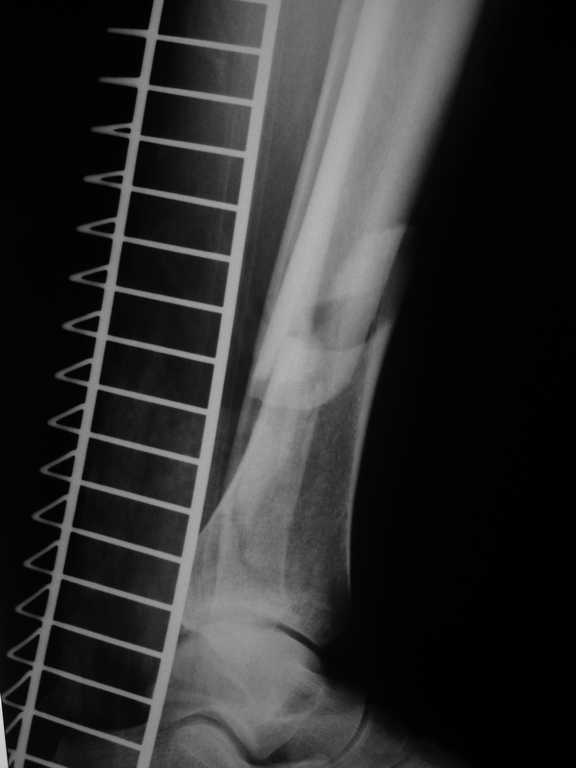

1. Ilizarov frame as definitive managment (it is crucial to perform high-quality about ankle fixation for early distal ring removing and ROM restoration) - see photo.

I've sent you picture of the leg. I have problem with this patients because he has had dyspnoea, hemoptysis. We have made, ABG, X-Ray, etc and finally angio-CT of thorax. Our diagnosis is fat embolus syndrome with some kind of acute lung injury (moderate hypoxia)

Now, he has had 3rd debridement in medial part of the leg, but his problem is also in lateral part - Morel - Lavalle Lesion...

In Friday I hope to stabilize ankle fracture. And then I plane to make acute shortening after remove all necrotic tissue from lateral and posterior compartment.